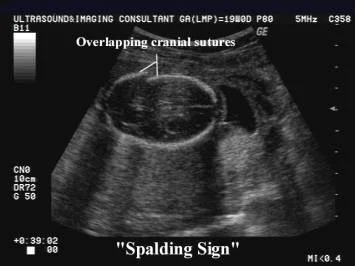

Skull bones show loss of alignment, and they override each other due to shrinkage of the brain after death, known as Spalding’s sign. The brain becomes pulpy and grayish-red in color.